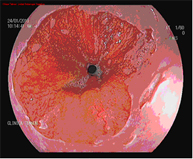

Diagnosis is performed using high-resolution magnification endoscopy (image enhancement), employing additional chromoendoscopy techniques conducted by endoscopists specialised in the early diagnosis of premalignant lesions, with targeted biopsies for analysis.